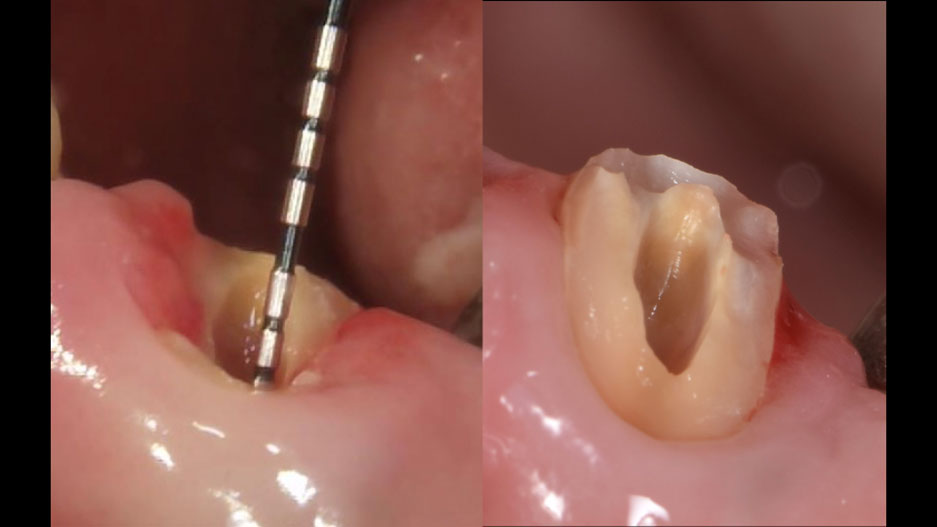

症例2 精密歯内療法で

抜歯を回避した症例

• 主訴

他院で抜歯と言われた/腫れ痛みが続く/膿が出る

• 診断

慢性根尖性歯周炎、根管治療不良

• 治療

マイクロスコープを用いた精密歯内療法

感染根管の再治療

最終補綴

• 治療期間

1.5〜2ヶ月

• 治療費

約14万円

• リスク

再発の可能性あり

歯質量が少ない場合は破折の可能性あり

精密歯内療法で抜歯を回避した症例

before    after